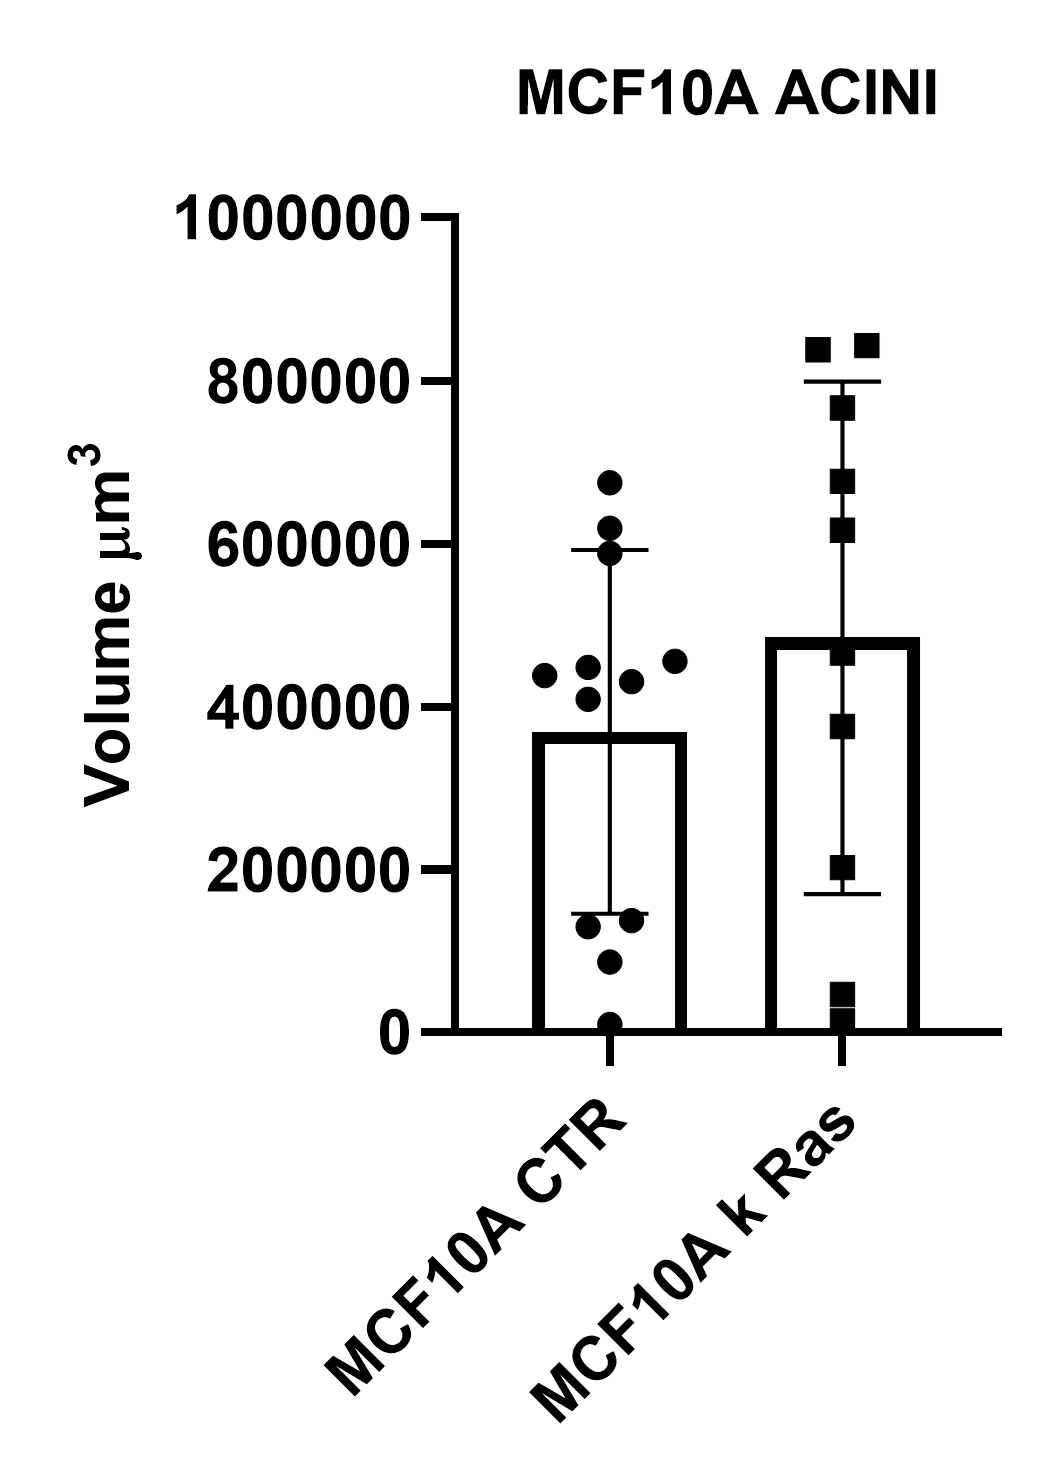

Using such an automated analysis pipeline, we have collected a wide range of information useful in understanding how mutated Ras receptors affect the proliferation and morphology of acini. As shown in Figure 8A, acinar structures from cultures of non-malignant breast cancer typically have round symmetrical shapes. On the other hand, the acini from malignant breast cancer cultures cause a deformation in the 3D architecture which causes the shape of the acini to be more elongated and deconstructed. Notably, the spheroids derived from the MCF10A K-Ras engineered line has a significant volume increase compared to the control line (Figure 8B). In fact, the transforming contribution of the k-Ras oncogene correlates with the increase in the cellular proliferative rate, and this causes an increase in volume already after 6 days in culture.

B

Figure 8: Representative MCF10A-CTR and MCF10A-RAS acini (A) and volume analysis (um3) (B). Cells were cultured in 3D Matrigel suspensions and stained with pericentrin (red) and DAPI (blue). This image was acquired with a CFI Plan Apochromat Lambda D 20x air objective (20x, Nikon, 0.8 NA and 0.8 mm WD). Volume comparison between MCF10A-CTR and MCF10A-RAS acini (B).

This powerful imaging system, coupled with software capable of automating acquisitions and analyses, made it possible to compare morphological characteristics between non-malignant (CTR) and malignant (K-Ras) cancer cells. Studying some morphological features such as volume, elongation, sphericity, diameter and surface, we found that malignant cancer spheroids display a loss of cell polarity during proliferation that alters acinar structure and architecture. 3D cellular models, therefore, are useful tools for re-creating in vitro tumor pathological phenomena. The combination of high-content microscopy with 3D cell models could thus contribute significantly to cancer research, especially in the validation of oncologically relevant molecules.